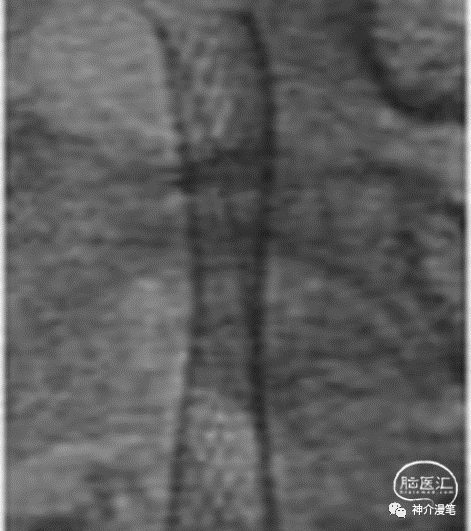

这个病例中,血管局部走行角度较大,wallsten植入后过多的改善了血管走行,让本来弯曲的血管变成一根直棍,一方面会增加局部血管的刺激造成再狭窄,另一方面血管皱褶的力度会向远端传导,造成远端血管走行变化甚至皱褶。这也是wallstent支架术后再狭窄率相对较高的重要原因,因此需要选择合适病例

当然对于这种血管条件较好的情况下,选择所有的支架都是合理的。